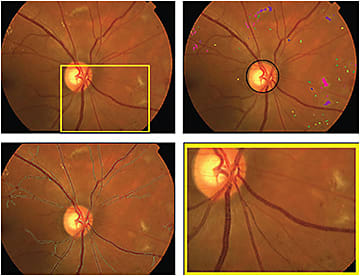

Fundus imaging biomarkers from a subject with diabetes and diabetic retinopathy. Input fundus color image (top left); lesion load metrics for hemorrhages (greenish), microaneurysms (yellowish), exudates (pinkish), retinal infarcts (purplish): the color shades indicate the confidence in the lesion type, and structural analysis of the disc location (top right); vessel analysis with green vessel boundaries (bottom left); detail of vessel analysis with local vessel widths visualized (bottom right).

COURTESY CHRISTINE N. KAY, MD, ELLIOTT H. SOHN, MD, AND MICHAEL D. ABRÀMOFF, MD, PHD